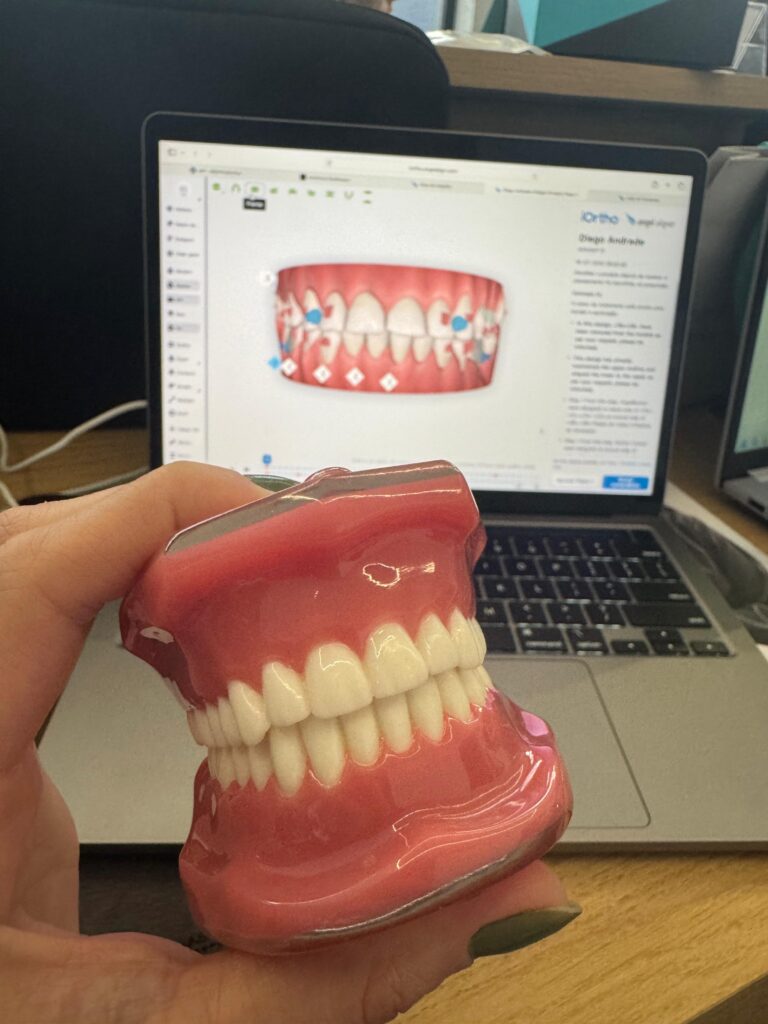

08:30 – Dispositivos associados aos mini implantes: MARPE, cantilever, distalizadores, elásticos, intrusão, retração e expansão

09:50 – Hands-on Parte 1: inserções em manequins/blocos de osso artificial em diferentes regiões

14:00 – Hands-on Parte 2: montagem de dispositivos associados (MARPE, distalizadores, cantilevers)

08:30 – Casos clínicos comentados: estratégias de escolha do dispositivo certo para cada tipo de movimento

Nossos treinamentos são totalmente hands-on

Você aprenderá na teoria e aplicar 100% na prática